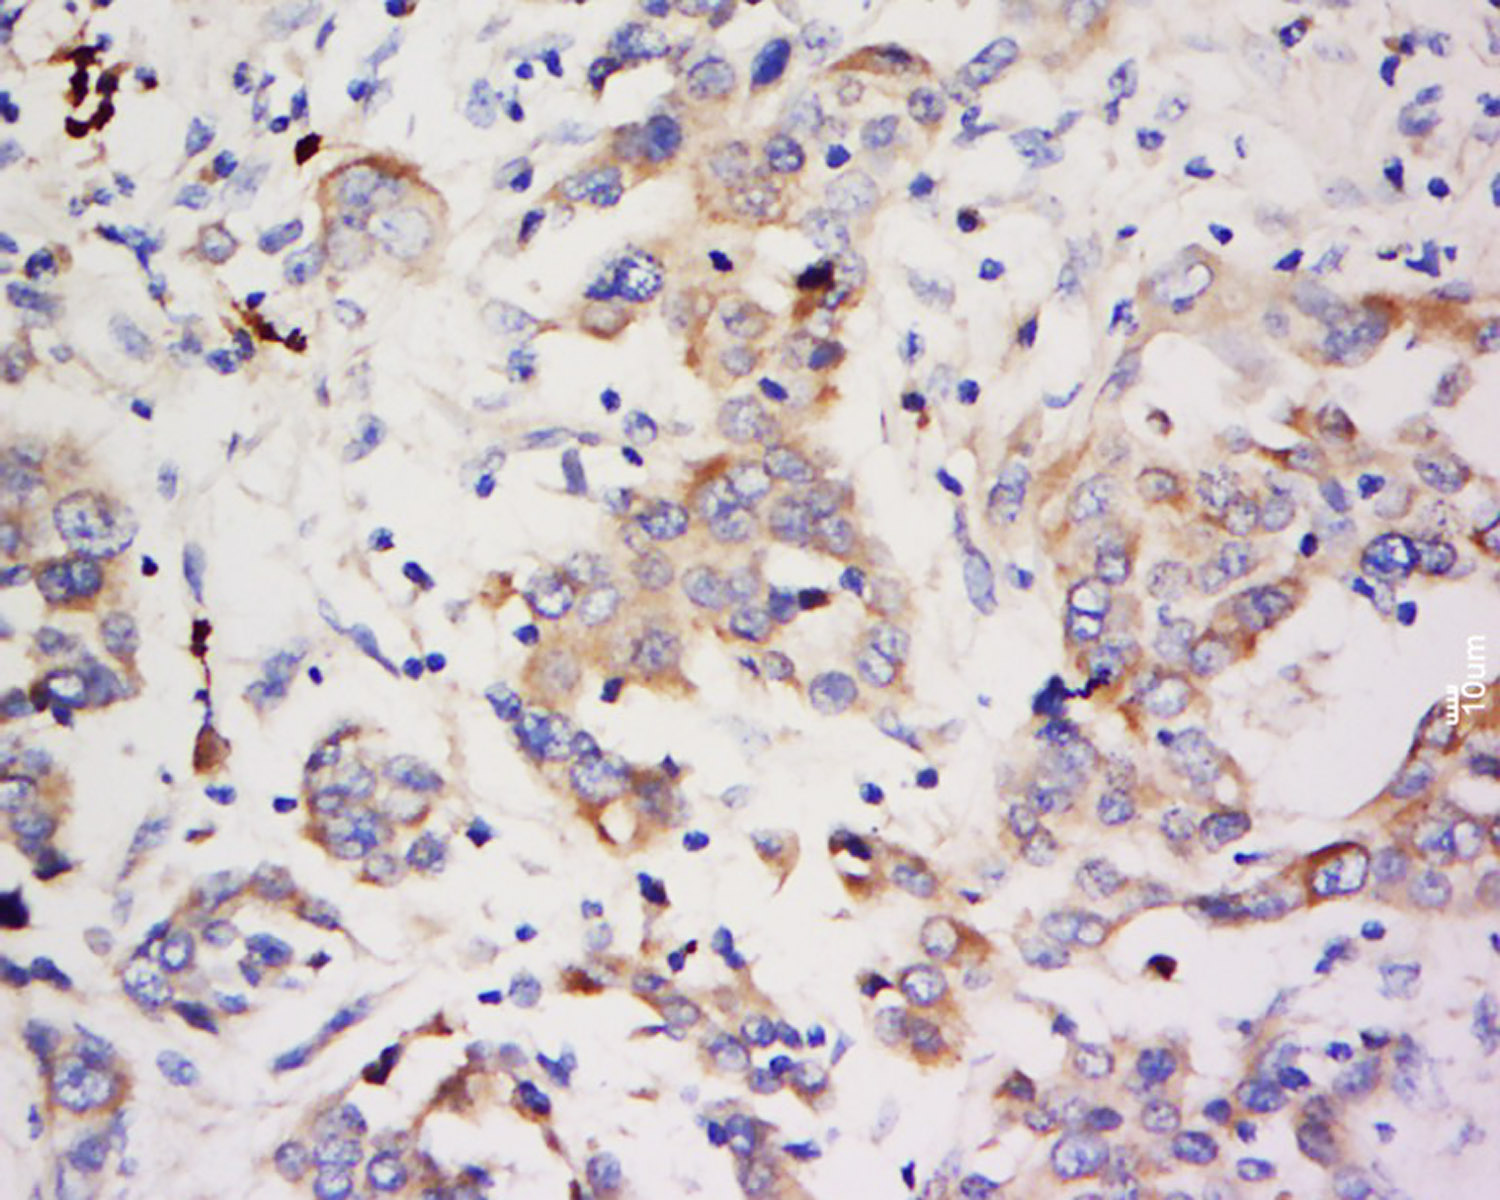

Tissue/cell: human breast cancer; 4% Paraformaldehyde-fixed and paraffin-embedded; Antigen retrieval: citrate buffer ( 0.01M, pH 6.0 ), Boiling bathing for 15min; Block endogenous peroxidase by 3% Hydrogen peroxide for 30min; Blocking buffer (normal goat serum,C-0005) at 37℃ for 20 min; Incubation: Anti-ZNF703 Polyclonal Antibody, Unconjugated(bs-20145R) 1:500, overnight at 4°C, followed by conjugation to the secondary antibody(SP-0023) and DAB(C-0010) staining